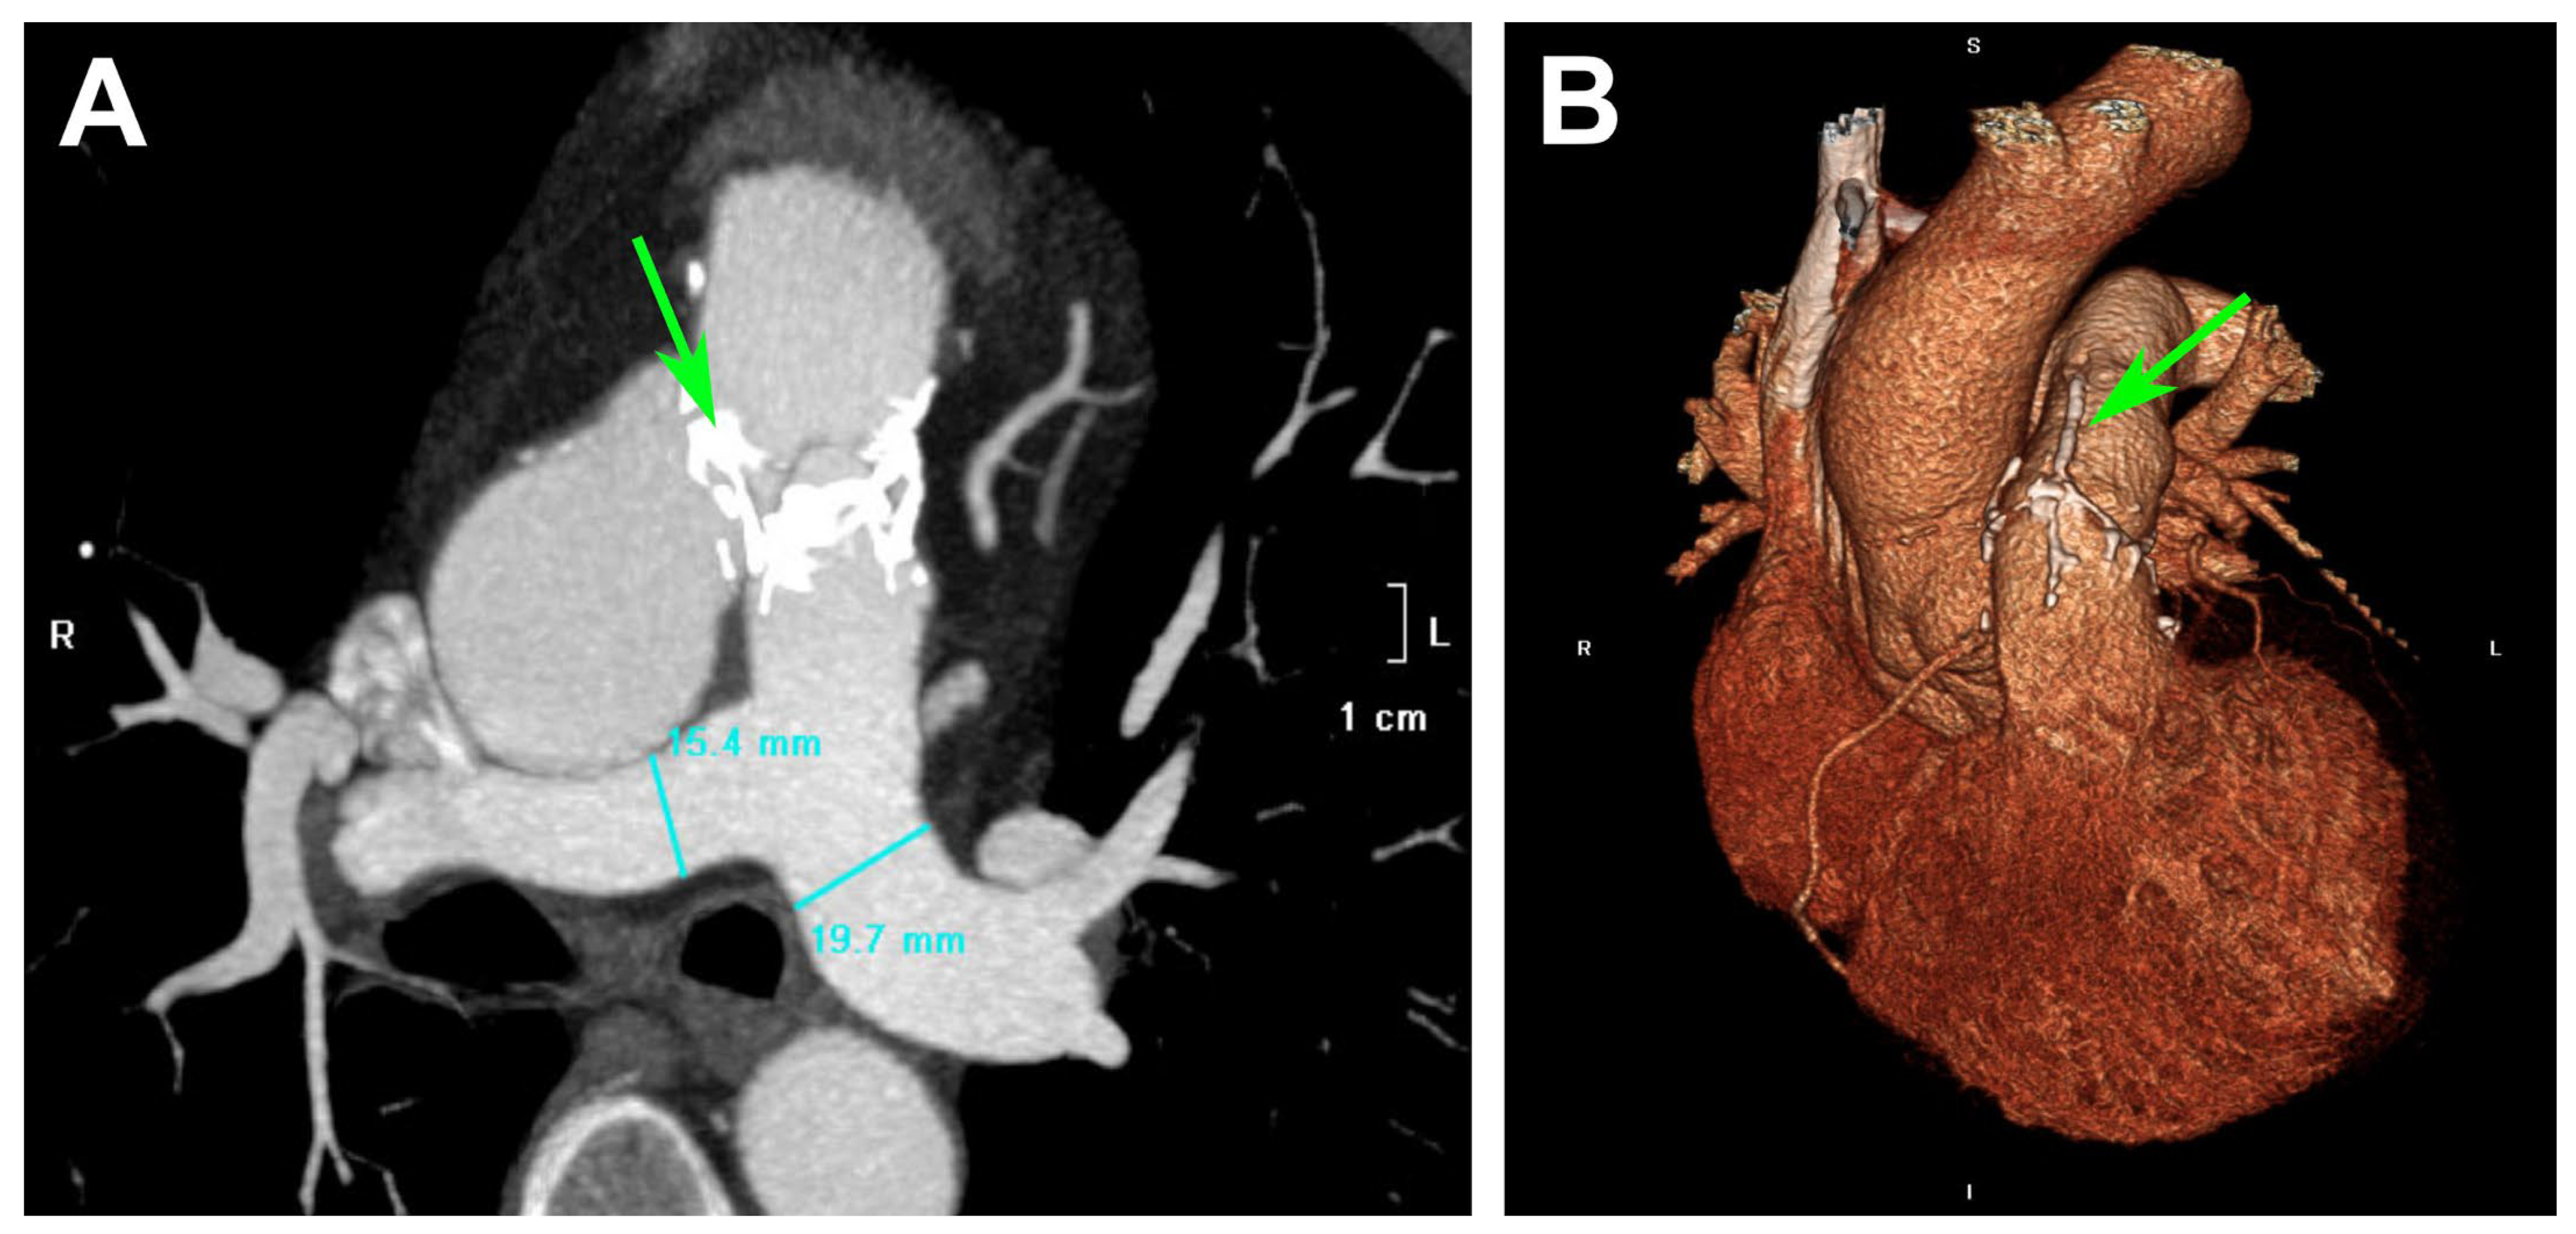

3.2. TEE Findings